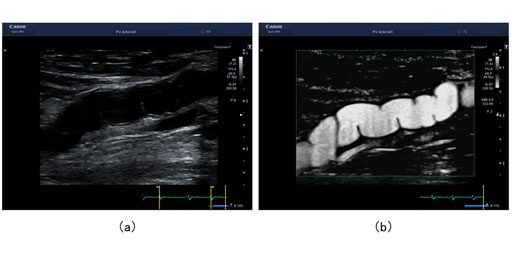

- 二重超音波:この検査では、高周波音波を使用して血管の画像を作成します。血管を通る血流の速度を測定できます。